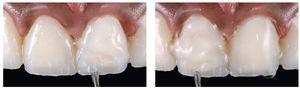

Figs. 31a y 31b. Las carillas laminadas cerámicas de disilicato de litio (e.max Press/e.max Ceram, Ivoclar Vivadent) sobre el modelo maestro. Las pequeñas carillas parciales en los caninos superiores se cuecen sobre un modelo pirorresistente (e.max Ceram).

En virtud del protocolo hemostático preciso con hilos finos, el tejido blando estaba sano al cabo de 21 días. Antes de la inserción definitiva de las restauraciones cerámicas se procedió a una prueba en boca para escoger el color ideal del cemento de resina. Tras la retirada de los provisionales se eliminó mediante discos de óxido de aluminio (Soft-Lex, 3M Espe, Seefeld, Alemania) la capa adhesiva que se encontraba en las superficies grabadas. Dado que se preparó únicamente en la zona del esmalte, fue posible llevar a cabo la prueba en boca del paciente sin anestesia.

A fin de obtener un resultado óptimo, los procesos de adhesión en caso de carillas laminadas muy finas requieren un alto grado de atención. En este caso se utilizó para la prueba en boca un material adecuado con una pasta, con objeto de escoger el color más indicado para el cemento de resina. La pasta para la prueba en boca es un gel de glicerina hidrosoluble que simula el resultado terminado. La figura 32 muestra la diferencia de color durante la prueba en boca.

Fig. 32. El color y la adaptación se comprueban mediante una pasta para prueba en boca a base de glicerina (Variolink Veneer Try-in Paste, Ivoclar Vivadent). Se probaron dos colores distintos: uno de baja claridad (LV-3) para el incisivo central derecho y uno con un grado de claridad elevado (HV+3) para el incisivo central izquierdo. El paciente participó activamente en la elección del color.

Se probaron distintos colores de pasta con mayor y menor intensidad (Variolink Veneer Try-in Paste, Ivoclar Vivadent). El paciente, el protésico dental y el odontólogo se decidieron de común acuerdo por un cemento de resina fotopolimerizable con un alto grado de claridad (Hohes Value HV+3, Variolink Veneer, Ivoclar Vivadent) para cementar definitivamente las restauraciones (fig. 33). El cemento de resina fotopolimerizable es preferible a las resinas de fraguado dual o autopolimerizables para el cementado de carillas laminadas, en virtud de su estabilidad cromática a largo plazo.

Fig. 33. Las cuatro carillas laminadas de los dientes anteriores realizadas en disilicato de litio se colocaron con una pasta de prueba en boca de gran claridad. Éste fue también el color de pasta finalmente seleccionado.